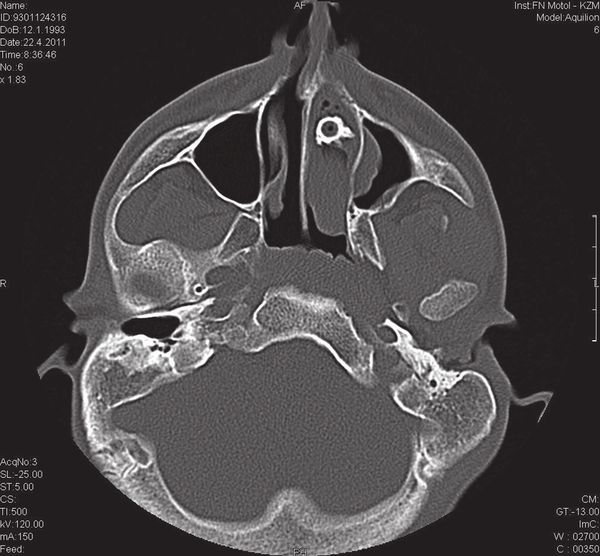

Чтобы тщательнее изучить структуры носовых пазух и выявить местонахождение чужеродного объекта, иногда используют рентгенографию и КТ. Рентгенография может быть полезна для выявления металлических или костных объектов, в то время как КТ обеспечивает трёхмерное изображение, что особенно важно при биологических рентгенпрозрачных инородных телах и тех случаях, когда предмет невозможно увидеть с помощью эндоскопа (если оно находится в толще мягких тканей) [7]. Также КТ позволяет уточнить характер и масштабы местных осложнений.

![Инородное тело в полости носа на рентгенографии [16] Инородное тело в полости носа на рентгенографии [16]](/media/bolezny/inorodnoe-telo-nosa/inorodnoe-telo-v-polosti-nosa-na-rentgenografii-16_s_nllnyA5.jpeg)

Инородное тело в полости носа на рентгенографии [16]